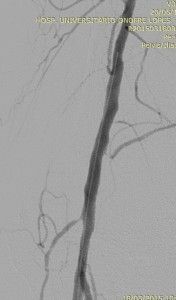

Um longo balão 2×150 mm de angioplastia foi introduzido pelo introdutor 5F agora passando a lesão por via anterógrada. O guia foi mantido também exteriorizado na perna servindo assim como “varal” para dar mais apoio na ultrapassagem da lesão. Após o correto posicionamento do balão, a angioplastia foi realizada com sucesso conforme evidenciado nas imagens abaixo.